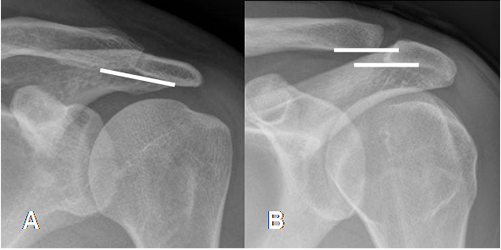

Fig 52. Articulación acromioclavicular.

A: Rx AP. Alineación normal de la articulación acromioclavicular.

B: Rx AP. Desalineación de la articulación acromioclavicular, que puede ser un hallazgo normal o patológico.